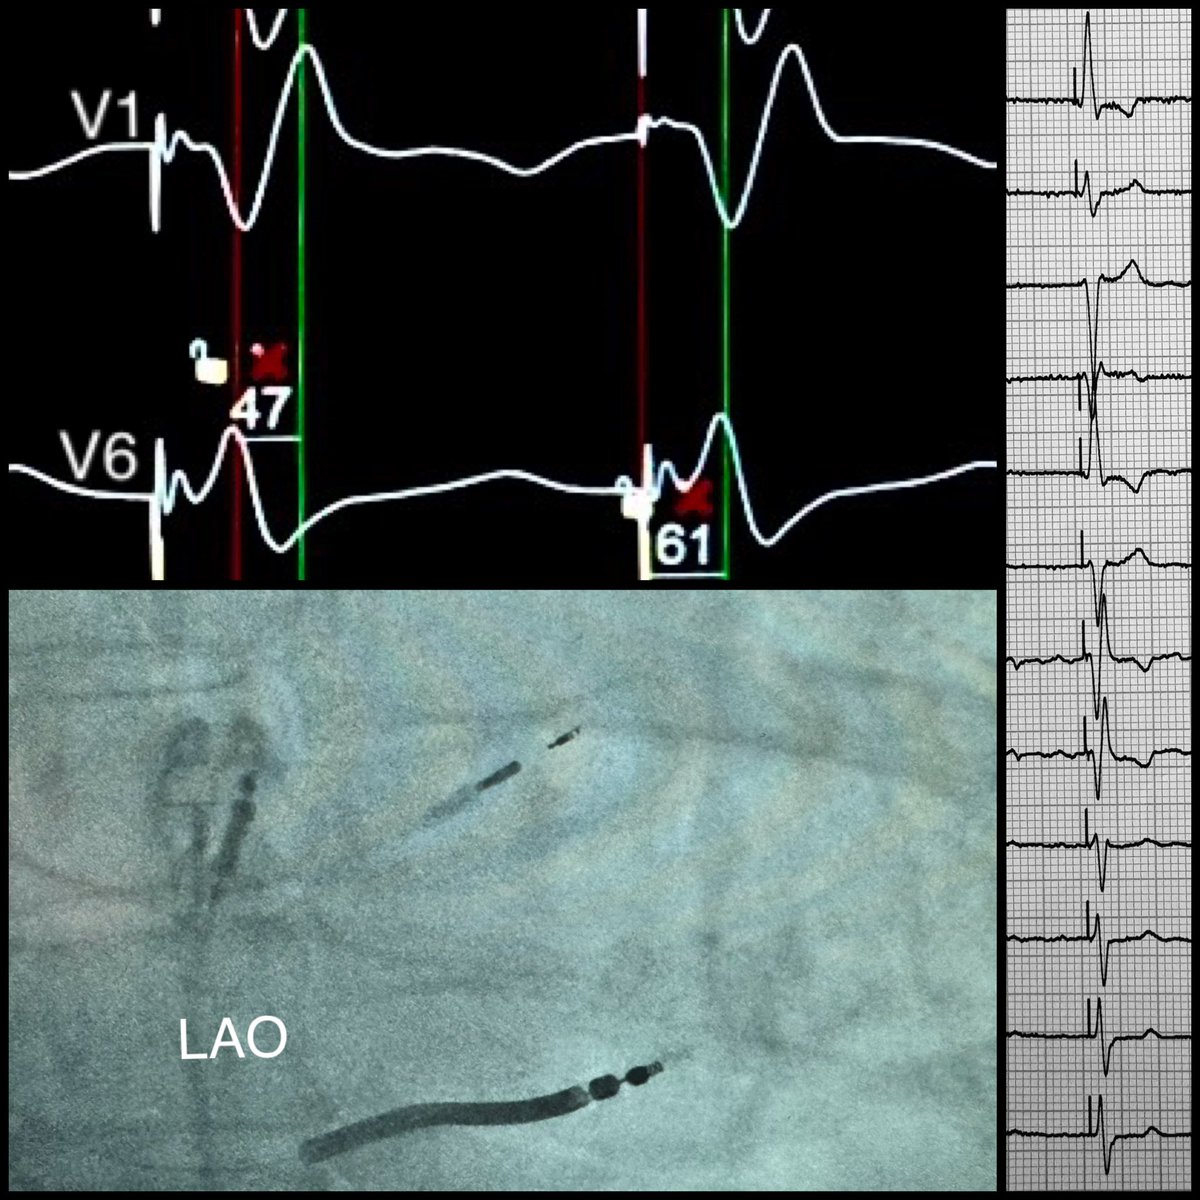

LBBAP in a NICM patient with severely enlarged LV and symptomatic AF. Going for pace & ablate strategy-aiming for physiologic pacing and better long-term outcomes. CRT alternative with a twist! Athanasios Saplaouras Ourania Kariki Stelios Konstantinos Letsas Michail Efremidis #EPeeps #LBBAP #OCSC

LBBAP in a NICM patient with severely enlarged LV and symptomatic AF. Going for pace &amp; ablate strategy-aiming for physiologic pacing and better long-term outcomes. CRT alternative with a twist!

<a href="/athsaplaouras/">Athanasios Saplaouras</a> <a href="/Kariki_O/">Ourania Kariki</a> <a href="/SteliosDragasis/">Stelios</a> <a href="/K_Letsas/">Konstantinos Letsas</a> <a href="/MEfraimidis/">Michail Efremidis</a>

#EPeeps

#LBBAP

#OCSC